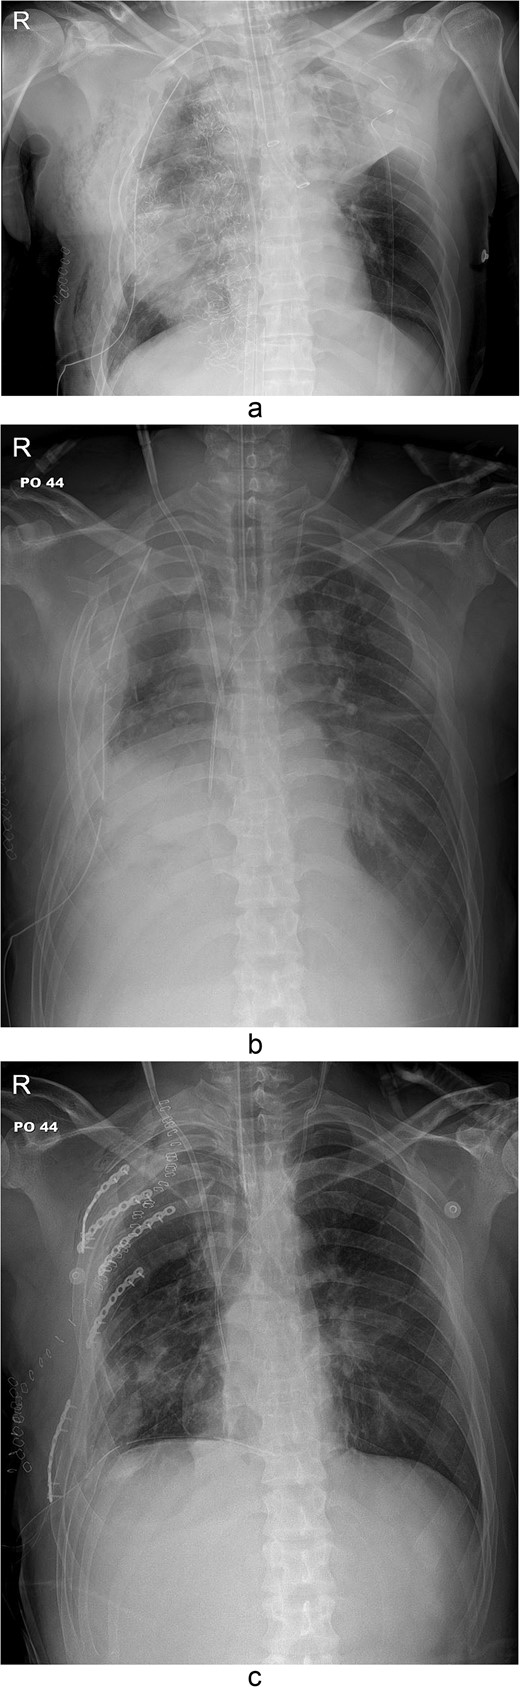

The thoracotomy incision was relatively small, ~8 cm in size, and the intercostal space was not spread to prevent further intraoperative chest wall damage. There were multiple lung lacerations in the upper, middle, and lower lobes with active bleeding. Bloody leakage continued through the avulsed parietal pleura and mediastinum. Hemostasis was achieved by suturing the deeply lacerated lung and packing with gauze (Combat Gauze ™ [Z-Medica QuikClot]) at the chest wall and mediastinum. The operation took 130 minutes. The transfusion of plasma, platelets, and red blood cells was balanced according to the following quantities: 10, 10, and 14 U, respectively. After surgery, the patient was transferred to the intensive care unit (ICU). The PaO2/FiO2 ratio was 52 mmHg with a Positive end expiratory pressure of 15 cm H2O, at a peak inspiration pressure of 30 cmH2O. ABGA showed pH 7.23, pCO2 42, and pO2 47. Veno-venous ECMO based on bilateral femoral vein cannulation was performed (Fig. 3a). Considering the patient’s hemorrhagic predisposition, heparin was not used. Disseminated intravascular coagulation (DIC) occurred along with acute renal failure. Antithrombin III infusion and continuous renal replacement therapy (CRRT) were initiated on the second hospital day. By the 5th day, oxygenation was achieved without ECMO support, followed by decannulation. On the 6th day, the second operation was performed in about 35 minutes. The gauze was removed, and no active bleeding or oozing was seen (Fig. 3b). The third operation, performed on the 13th day, was an open reduction of right ribs 3–7 for correction of flail chest and took 75 minutes (Fig. 3c). After open reduction, the flail chest improved, but the patient was not able to be weaned off the ventilator. Pneumonia and bacteremia developed. A tracheostomy was performed on the 15th day. CRRT was switched to hemodialysis, which was stopped on Day 28. The patient was discharged on the 47th day without tracheostomy. Ten months postoperatively, pulmonary function testing revealed forced expiratory volume in one second and diffusion capacity of carbon monoxide of 77% and 67% of predicted values, respectively. The chest CT and radiographs showed that the lungs had healed well, and there was no displacement of the ribs (Fig. 4). The patient recovered and returned to work.

Simple radiographs obtained after each operation. (a) Radiograph after the first operation. Gauze, which is visible as a wavy white line, was packed in the right thoracic cavity. Multifocal opacity was seen in the right lung, and there was left upper lung atelectasis. ECMO catheters were placed in the IVC. (b) Radiograph following the second operation. The right ribcage is narrowed due to displaced fractured ribs. (c) Radiograph after the third operation. Five plates were applied to the fractured ribs.